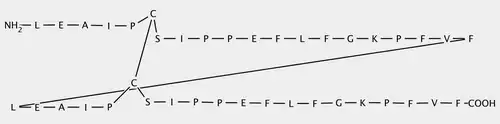

The VIR-576 is a peptide.[7] Consequently, it is a molecule formed by a sequence of amino-acids united by peptide bonds. If we compare both primary structures, it can be seen that the VIR-576 has 2 subunits. Each subunit, monomer is a variant form, a mutant of the VIRIP,[1] differing from four amino acids.

Thus, among the new ones introduced, it is important to emphasize the importance of the cysteine (C) introduced replacing the methionine (M), both being sulfated amino acids, in the stabilization of its structure.

Another important interaction that we must underline is the disulfide bond established between both cysteines of the two monomers of the VIR-576 which allows the peptide to have more structural stability in the space in comparison with the VIRIP. Moreover, the ring form that appears in the secondary structure is due to this interaction between both sulfate atoms. Thanks to this disulfide bond, a cystine is formed. This fact allows the union of the subunits during the reaction with the gp41 and also allows them to act simultaneously. Thanks to all this activity and to the dimerization respect to the VIRIP, the VIR-576 is more effective.[10]